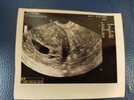

Znalazłam

Byłam 7+4. USG tego samego dnia, dwóch lekarzy i dwa sprzęty różne. Wg jednego 7+3, a drugiego 6+1. 🤣 Oczywiście najpierw miałam to gorsze i zryczalam się jak bóbr, szykowałam na poronienie i łyżeczkowanie 🤦 poleciałam szybko do super kliniki z super sprzętem i wszystko ok, maluch nie tylko mial serduszko, ale ruszał się... To było cudowne.

W każdym razie chodzi mi o to, że zobacz ile daje sam sprzęt. A do tego te maluchy w 6 tygodniu to mają koło pół centymetra. :D także na spokojnie. :)

• IMG_20211213_093317 (1).jpg

IMG_20211213_093317 (1).jpg

64,8 KB · Wyświetleń: 146